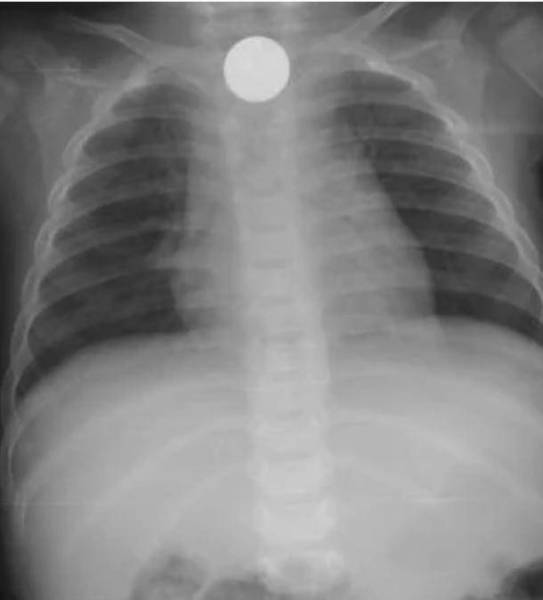

نجح فريق طبي بمستشفى المهد العام، من استخراج قطعة معدنية، من أعلى مريء طفل يبلغ من العمر 6 سنوات، في عملية استغرقت 4 دقائق فقط.

وأوضح الفريق الطبي، أن الطفل قدِم لطوارئ المستشفى وهو يشتكي من بلع جسم غريب (قطعة نقود معدنية)، كانت قد عَلِقت في أعلى المريء، ما تَسَبّب في اختناق وعدم القدرة على البلع، عندها قرر الفريق الطبي إجراء عملية عاجلة، واتضح أنها قطعة معدنية نقدية فئة «ريال»، مضيفاً: «تمت العملية بنجاح ودون حدوث مضاعفات ولله الحمد، حيث غادر الطفل المستشفى وهو بصحة جيدة».